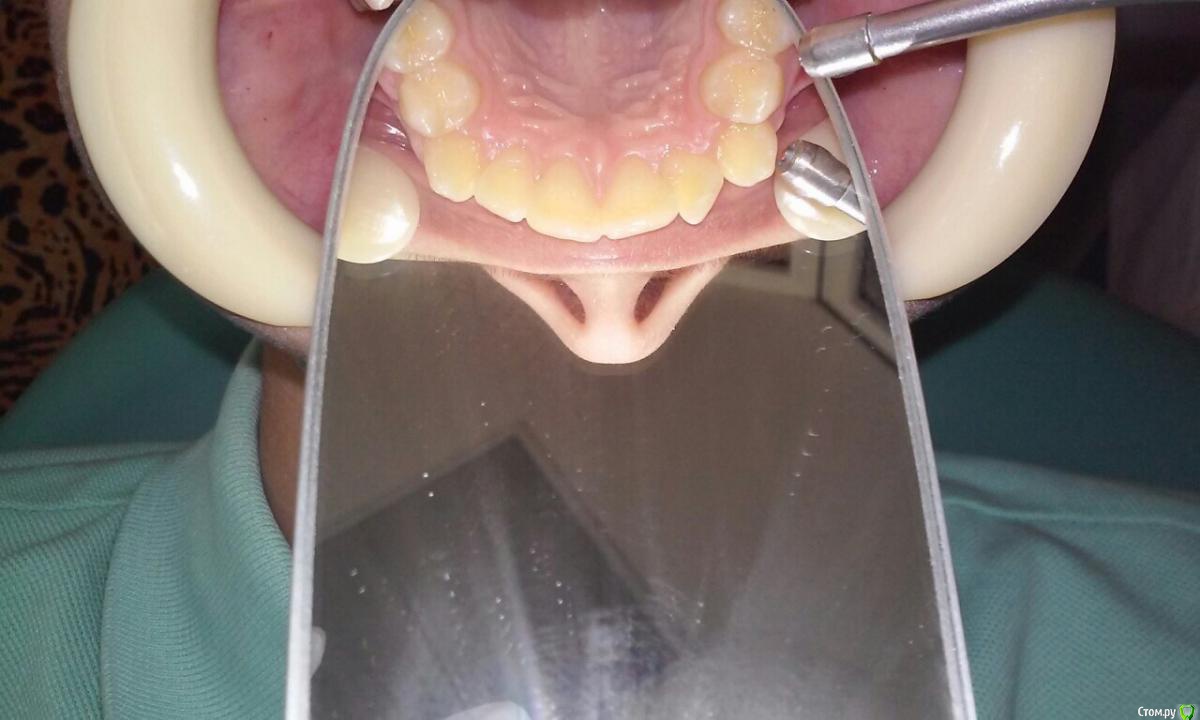

natkoorth1991 Опубликовано 28 августа, 2015 Поделиться Опубликовано 28 августа, 2015 мальчик, 13 лет, премоляры удалять не хотели, поставила хайракс на в / ч- получила перекрестную окклюзию. Извините за плохие фото( Что теперь делать? фото после: Ссылка на комментарий

Molox Опубликовано 29 августа, 2015 Поделиться Опубликовано 29 августа, 2015 Выведете. Наверх поставьте зауженную дугу, на низ - стандартную или широкую. Поскольку диастемы не появилось, у меня стойкое подозрение, что расширение было зубоальвеолярным, значит на брекетах вернуть все можно. Скажите, а зачем вообще аппарат ставили? Дефицит места минимальный, десна хорошая; на брекетах за 6 мес все бы расправилось. Ссылка на комментарий

Yana guapa Опубликовано 29 августа, 2015 Поделиться Опубликовано 29 августа, 2015 конечно, показаний для PRE здесь не было. но раз уж поставили, то поставили.Я бы теперь скручила винт в обратную сторону. будет нужный результат. Потом сняла бы аппарат и просто сделала бы перерыв. Премоляры сами немного вернуться к исходному положению Нет ТРГ. Но стакой инклинацией верхних центральных резцов могу предположить, что НЧ смещена кзади. Если это выяснится, и в ходе лечения НЧ будем перемещать вперед, то это тоже поспособствует лучшему смыканию. ждем снимков 2 1 Ссылка на комментарий